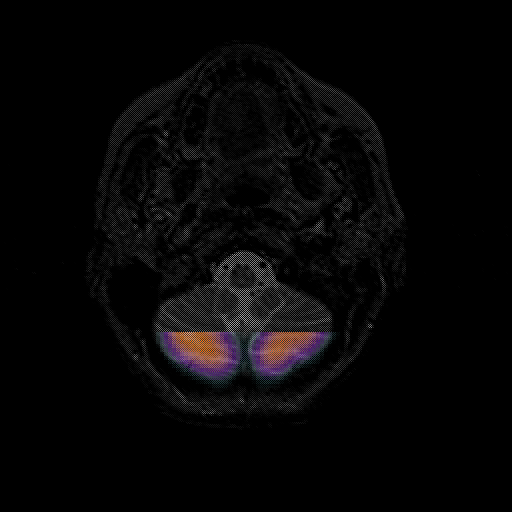

overlay 1: Slice 6

Slice 6

MRCBFCBF with

T1PDT2T1PDT2